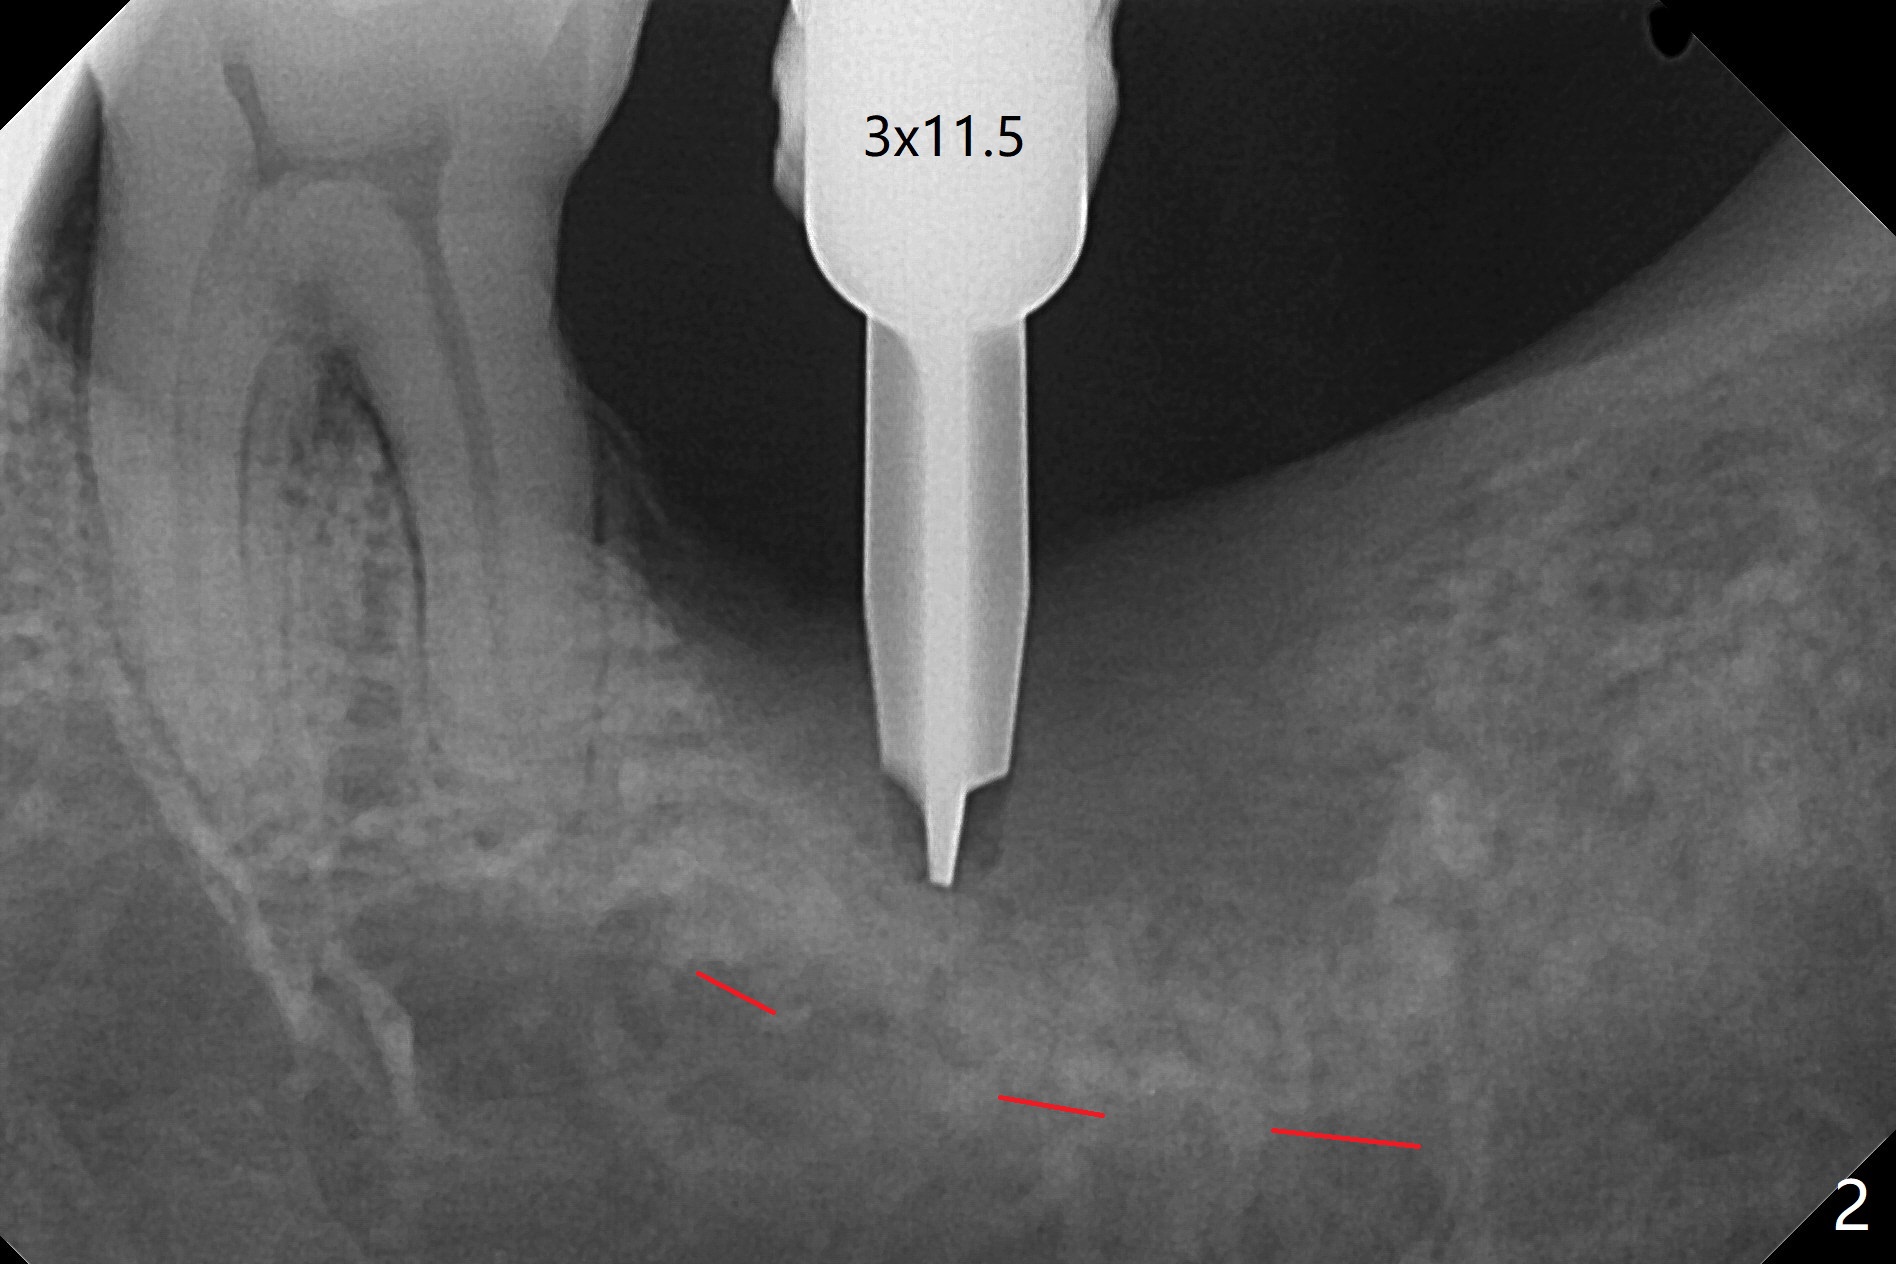

病人回来左下7拔牙植牙,十分感激导板取模后松动牙固位(图一),让他能正常吃饭。去除颊侧树脂和钢丝,6,7之间树脂自动脱落。拔牙后,肉芽组织很多,需要把局麻药注射至肉芽组织中,刮除时不慎远中舌侧牙龈穿孔。尽管纱布压迫,渗血相当多。怀疑导板就位不全,没有纠正。完成钻洞,报废植体无法就位。放置最后一个钻头,根尖片显示钻洞太浅了(图二)。再次磨除6颊侧,远中树脂,导板好像就位,重复钻洞,仍旧太浅(图三),CT表明钻洞偏颊侧(图四)。准备徒手改变钻洞,但是病人疼痛,只好植骨(粘性骨粉)(图五),牙槽窝舌侧,咬合面各覆盖一张PRF膜(图六:箭头),牙间隙维持器和牙周敷料固定。导板在曾经有树脂地方必须缓冲(图七:6;八:*,与图一对比),磨除深度有时不准确。术后两周牙周敷料仍稳定(图九),虽然病人希望撤除,我们偏向保留。反正病人正在做局部牙齿矫正。术后三周牙周敷料脱落,左上6咬合面树脂为了对侧局部牙齿矫正(图十)。骨粉有些丧失(图十一),最好手术时使用不可吸收膜。术后四个月牙槽窝充满骨粉,可以在下齿槽管颊侧植入4x8.5毫米植体(图十二)。